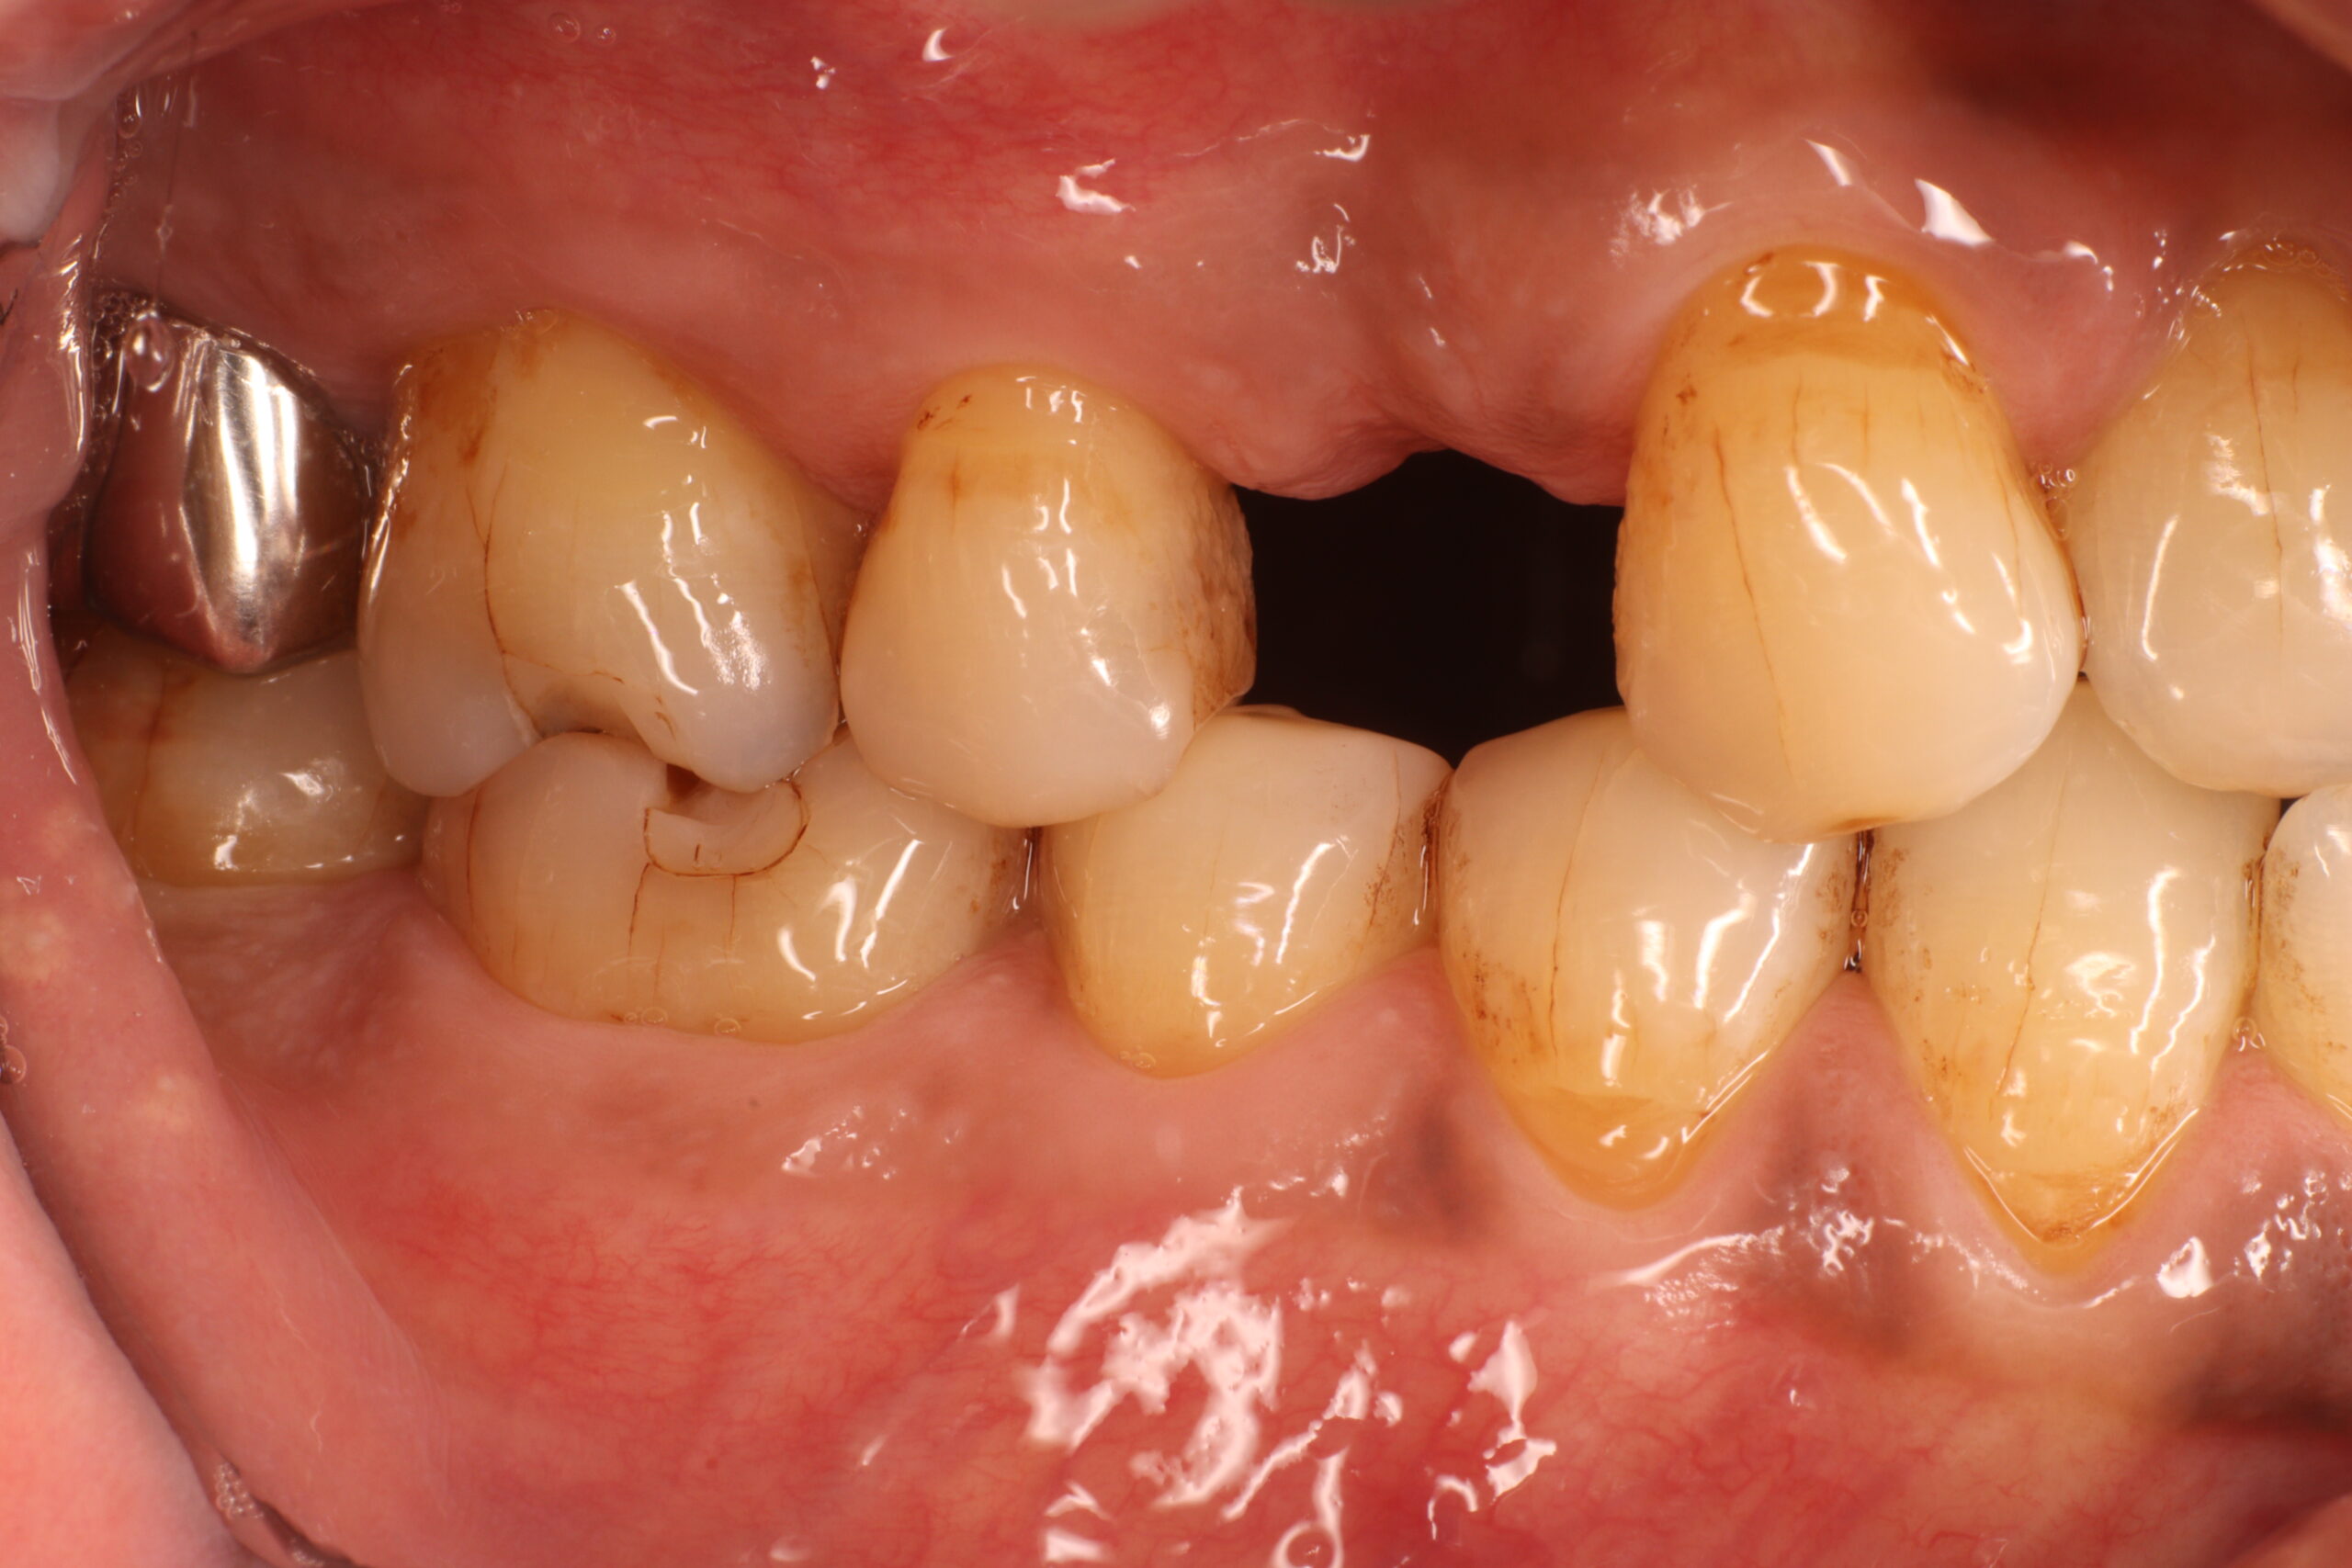

Before

| 主訴 | 歯が折れたので見てほしい |

| 診断名 | 歯根破折 |

| 年齢・性別 | 50代・女性 |

| 治療期間・回数 | 6ヶ月~1年・5回 |

| 治療方法 | 待時インプラント |

| 費用 | 400,000円~450,000円【税込み】(インプラント1本あたり) |

| デメリット・注意点 | ・保険適用外の自由診療範囲となるため治療費が保険診療より高く感じる場合があります ・外科手術が必要になるため、患者さんに体力的な負担がかかります ・段階的に治療を進めていくため、治療期間が長くなります ・術後に痛み・腫れ・出血・合併症を伴う可能性があります ・術後も定期的なメンテナンスをしないと、機能が落ちやすくなります |